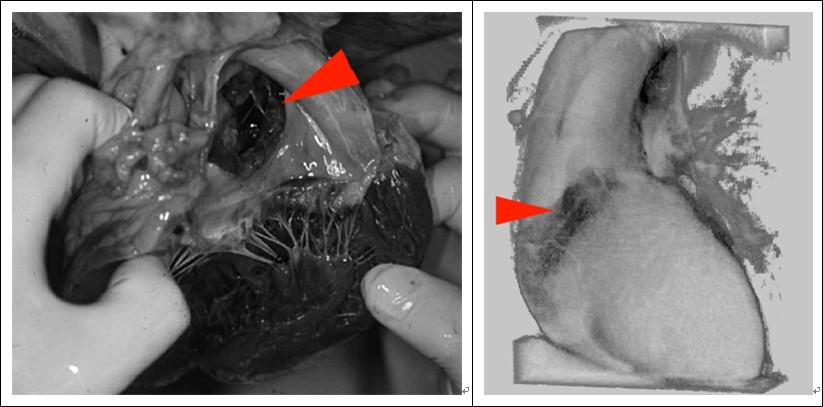

(14)IDL在法医诊断中的应用

传统的法医诊断采用直接解剖的方式,这样可能造成潜在信息的损失。应用IDL通过受害者的CT或MR影像和其它数据,可以进行多种形式的三维重建,辅助法医进行死因的决策分析。

Fig 14:解剖图和应用IDL进行三维重建后图像的对比